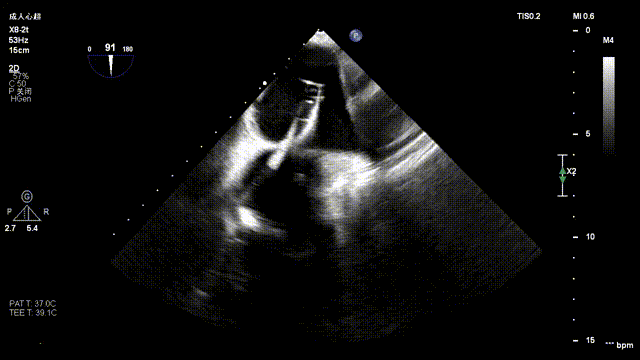

The operation was performed in a hybrid operating room and completed under the guidance of real-time three-dimensional transesophageal echocardiography (3D TEE) and X-ray fluoroscopy throughout the entire process.

Mitral Valve Repair Stage: Via the transfemoral venous approach, a 4.0 cm atrial septal puncture was performed, and one mitral valve clip was selected. The unique feature of wide-angle deployment effectively resolved the issue of excessive leaflet tension during valve clip closure. Under the precise guidance of ultrasound, one clip was successfully implanted at the site of the widest regurgitation in the A2-P2 segment of the mitral valve. Immediate postoperative TEE assessment showed that mitral regurgitation was reduced to trivial (1+), the mean transvalvular pressure gradient was only 3 mmHg, and pulmonary venous retrograde flow was significantly improved.

Intraoperative Imaging

Atrial Septal Puncture

Guide Sheath Implantation

Mitral Clip Trajectory Test

Orientation Confirmation

Orientation Reconfirmation After Transvalvular Crossing

Clip Closure Following Leaflet Capture

Regurgitation Essentially Eliminated at 25° Closure

Trivial Residual Regurgitation Post Deployment

Stable Tissue Bridge

Transvalvular Pressure Gradient of 3 mmHg